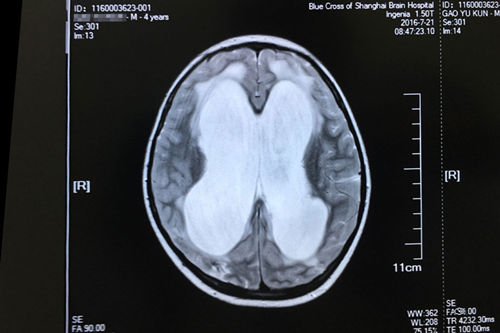

车祸昏迷74天后,亮亮来到了“蓝十字”。完善相关检查之后,神经外科主任侯增欣(政府特殊津贴专家)、原上海复旦大学附属华山医院神经外科专家潘仁龙主任,以及亮亮的主治医生副主任医师经过病情讨论会诊之后,给亮亮下的结论是:重型颅脑损伤、化脓性脑膜炎、脑积水、多发性骨折。侯增欣主任和其他专家一致认为:虽然亮亮的伤情严重,但治疗的希望还是有的。头颅MR显示:脑积水明确,各项检查完善,未见明显手术禁忌,可以开展“脑室-腹腔分流术”。

亮亮术前的磁共振影像显示:重度脑积水伴间质性脑水肿

手术前,侯主任召集本科室医生、麻醉科、脑电监测等相关医护人员进行了术前讨论,就手术中可能遇到的风险和问题进行了充分论述。由于患者伤情严重复杂,加上年龄较小,承受能力弱,所以手术可能出现全麻药物过敏,过敏性休克。术中和术后容易出现颅内出血,术后可能引发颅内感染,出现硬膜下积液,术后还有可能诱发癫痫发作等。对于这些有可能出现的问题和风险,各科室都谨慎做好了一切应对准备。